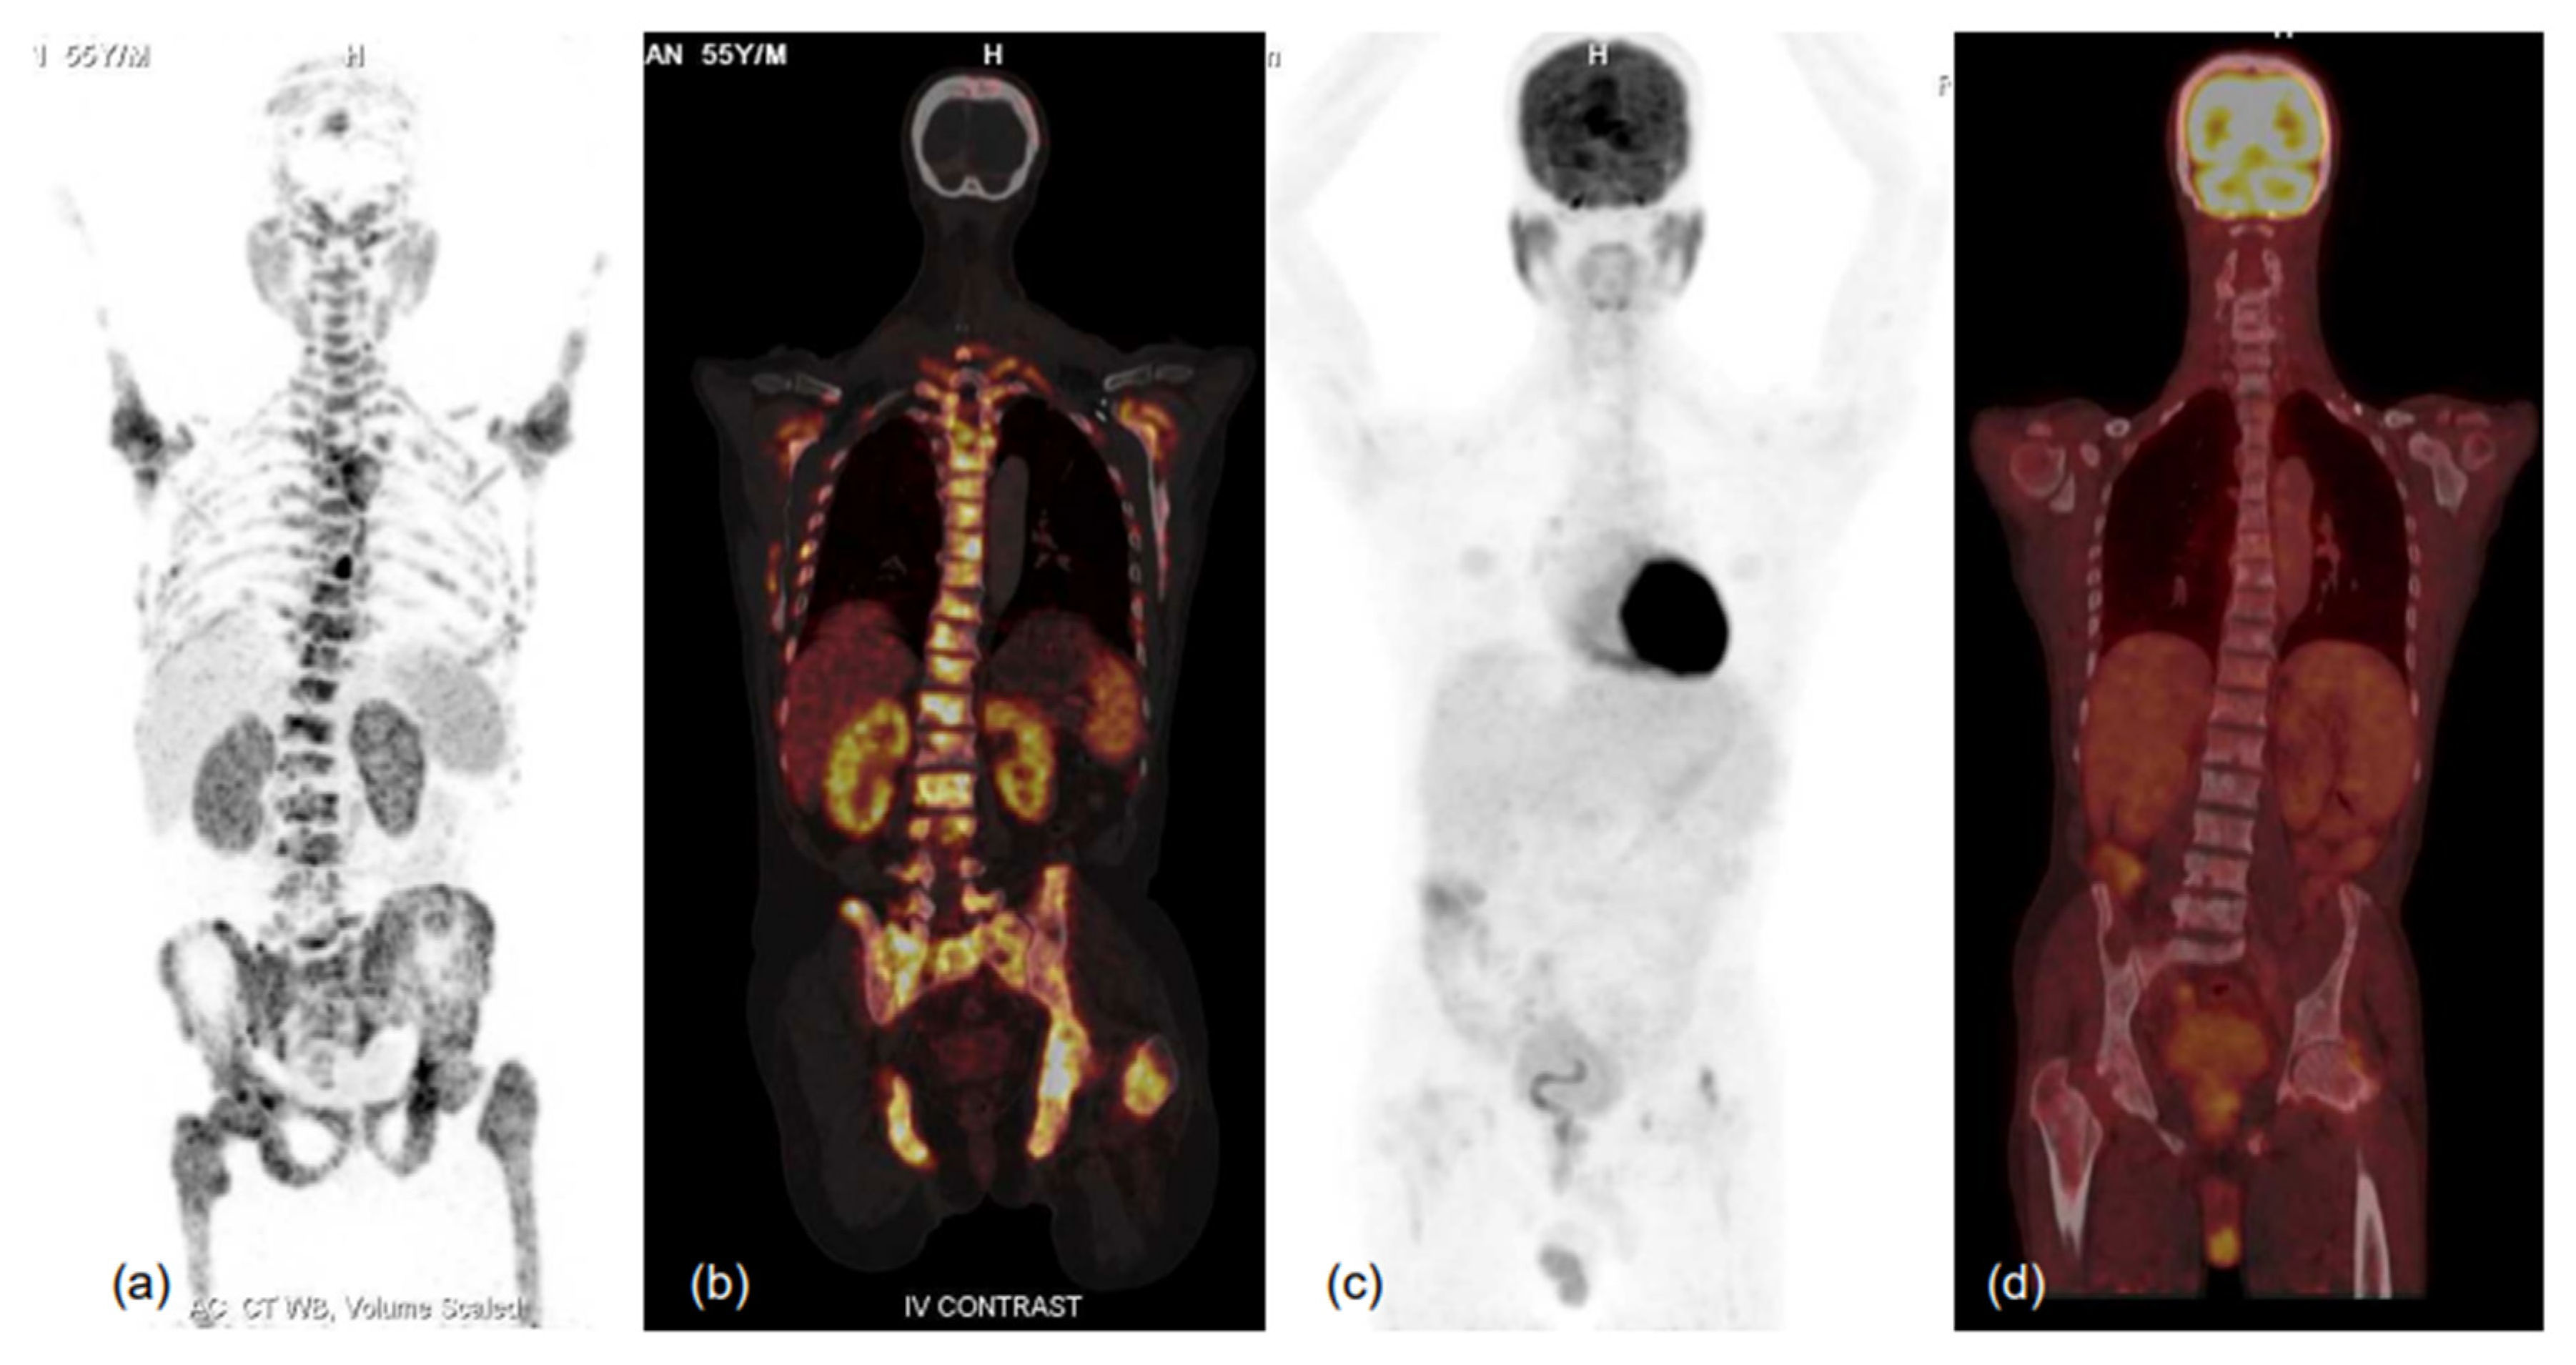

4. Primary Staging

5. Biochemical Recurrence and Metastatic PCa